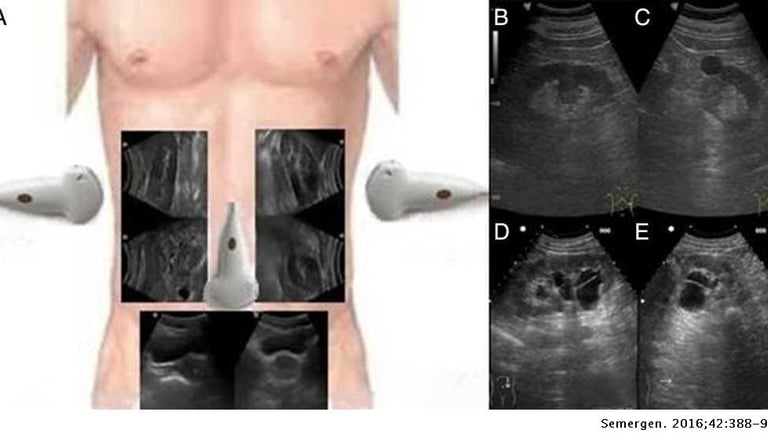

Ecografías

En IPS Santa Salud, Aguachica, Cesar, ofrecemos servicios de ecografía con tecnología de última generación, garantizando imágenes claras y diagnósticos precisos. Nuestro equipo de especialistas está capacitado para brindar una atención cercana y confiable, cuidando tu bienestar y el de tu familia.

Realizamos estudios ecográficos para diferentes necesidades médicas, asegurando resultados rápidos y confiables que apoyan tu salud integral.